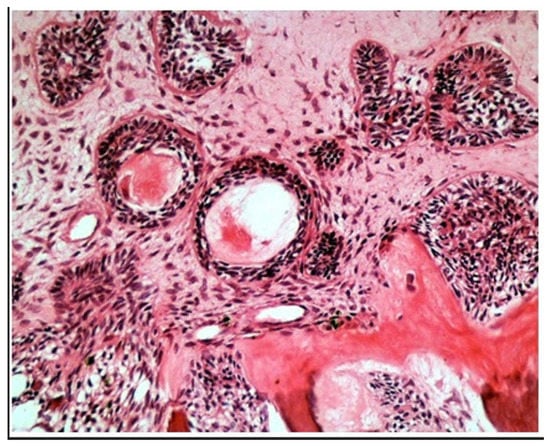

Treatment Possibilities in Mandibular Defect Reconstruction Based on Ameloblastic Fibro-Odontoma Treatment—Does Small Bone Defects Heal without Bone Grafting?

2. Case Report Presentation